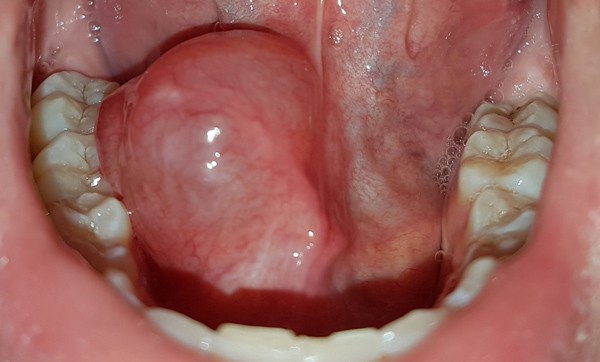

Un patient âgé de 23 ans consulte en urgence pour une tuméfaction sublinguale droite (fig. 1) évoluant depuis 48 heures, indolore, gênant l’élocution. Il ne présente aucun antécédent médico-chirurgical, mais rapporte avoir eu quelques épisodes de tuméfaction de petite taille sous la langue à droite, disparaissant spontanément. Aucun traumatisme récent n’est rapporté à l’interrogatoire. Il n’existe aucune adénopathie cervicale. L’examen endobuccal montre une volumineuse tuméfaction sublinguale droite ne dépassant pas la ligne médiane, sans signe d’inflammation, lisse, rose bleutée et souple. La muqueuse buccale est normale. La palpation de la glande submandibulaire droite fait sourdre de la salive claire à l’ostium du conduit submandibulaire (caroncule sublinguale). Il existe un sillon libre avec la table mandibulaire.

La lésion décrite est en faveur d’un kyste mucoïde du plancher buccal (syn. ranula ou grenouillette). En effet, la tuméfaction est d’apparition rapide, d’aspect lisse, bleutée, avec des antécédents de fluctuations [1]. Les kystes mucoïdes du plancher buccal peuvent prendre leur origine dans une glande salivaire accessoire ou se développer directement à partir de la glande sublinguale. Le développement peut se faire par extravasation ou par rétention salivaire.